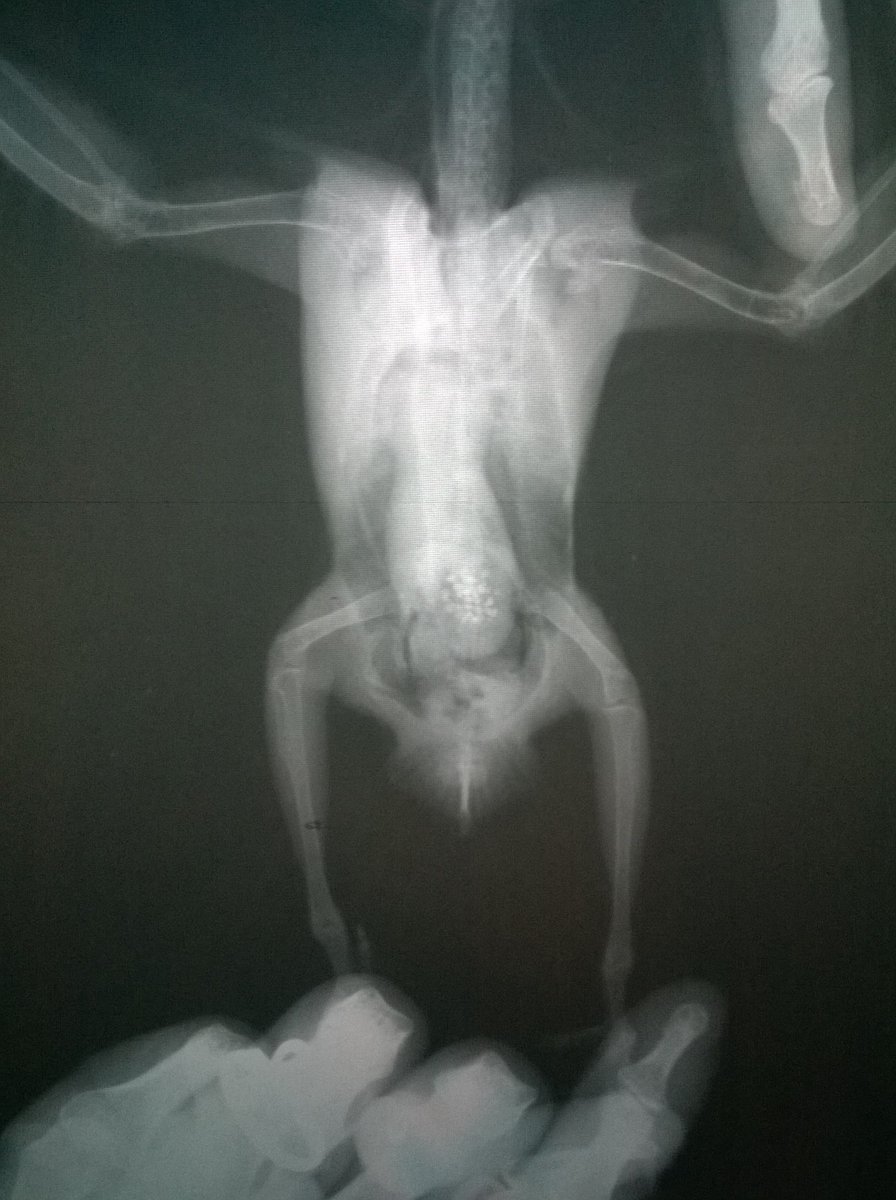

Возраст: 7 полных лет. Пол: женский. Порода: сизарь обыкновенный (Columba livia). Около 4-х месяцев назад голубка перестала нести яйца. Последние две пары снесенных яиц были значительно меньше обычных (не более 2 см.). Затем (в конце июля) появились странные выделения в помете (фото 1 и 2). Такие выделения начали выходить вместе с пометом примерно 1-2 раза в месяц. Когда у нее появляются эти странные выделения она ведет себя примерно так же, как во время кладки (хвост опущен, ищет место для кладки, разгребает, учащенно дышит). В остальное время голубка жизнерадостная и активная, ест и пьет хорошо, как обычно, летает, общается и т.д. Мы были у ветеринара, ей сделали рентген (фото 3 и 4). Доктор сказала, что у нее в брюшке эти сгустки - предположительно, остатки несформированного яйца. Эти сгустки могут накапливаться и давить на органы. Доктор предложила два способа решения: Инъекция (чего именно мы не знаем). При помощи этой инъекции, предположительно, голубка должна самостоятельно избавиться от этих сгустков, которые выйдут самостоятельно. Доктор сказала, что понаблюдает за ней в течение половины дня. Оперативное вмешательство. Если инъекция не подействует - доктор сказала что нужно будет делать операцию по очистке. Но при операции есть риск неудачного исхода. В общем от операции, над инъекцией думаем. Хотим собрать мнение еще нескольких специалистов, т.к. очень боимся возможного риска и не хотим сделать хуже. Пишу сюда, потому что хочу узнать мнения людей, встречавшихся с подобными ситуациями и так же мнения орнитологов и\или голубеводов, присутствующих на этом форуме. Заранее спасибо всем за ответ!- 3 ответа